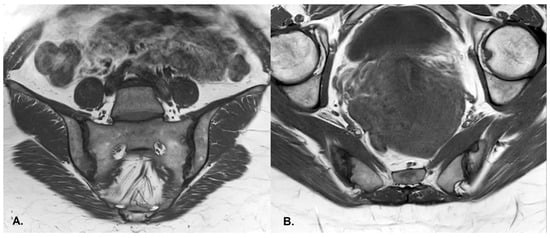

- BME is evident in low signal T1w, hyper signal T2w, STIR images and +C T1w Fat-Sat, similar to blood vessels and spinal fluid; the signal intensity is directly proportional to the inflammation activity. It is usually located periarticular to or on the subchondral bone surfaces and it is an indicator of disease activity (Figure 4) [65].

- Erosions–initially focal, later they will converge and will have a pseudo-enlargement aspect of the sacroiliac joint. In T1w images there is a loss of cortical bone signal (normally hypointense) and bone marrow fat (normally hyperintense).

- Sclerosis—better visualized on an X-ray or CT scan; a subchondral or periarticular area with a low signal compared to normal bone marrow on T1, T1FS (SPIR), and STIR sequences (Figure 5).Slight: <25% of the subcortical bone area.Moderate: 25% to <50% of the subcortical bone area.Severe: >50% of the subcortical bone area [29].